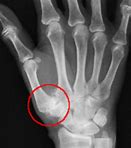

Pathologies